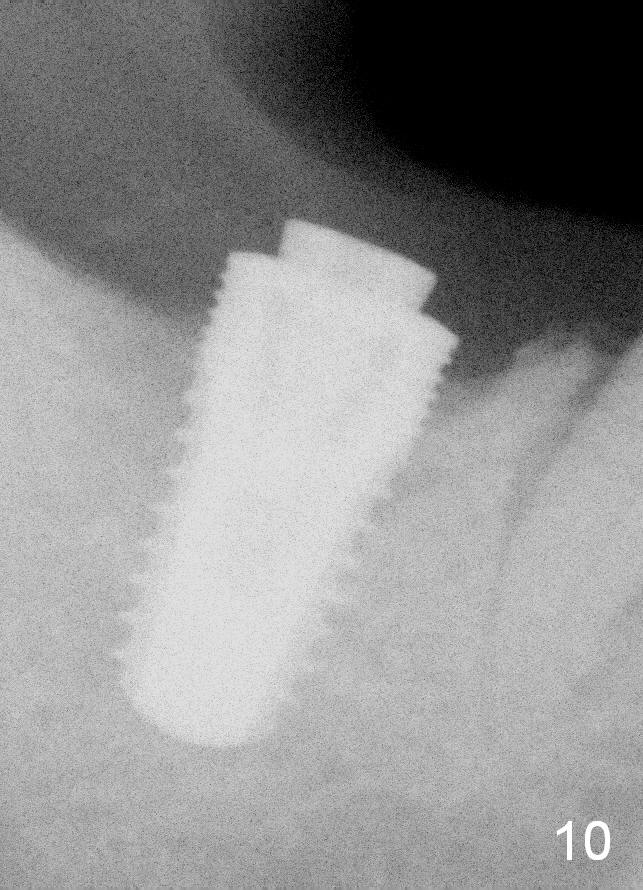

A 57-year-old lady returns for #31 implantation. The vertical edentulous space is limited, as the opposing tooth is supraerupted (Fig.1 arrow). Preop PA is critical (Fig.2), since it is used to measure the bone height (Fig.3: 12 mm). The length of the implant is expected to be 10 mm. The initial osteotomy depth is 8 mm (Fig.4); it appears that the trajectory should be adjusted. Osteotomy increases following depth and angulation adjustment (Fig.5: 4.5x10 mm drill). The submerged implant (5.3x10 mm) is placed with insertion torque approximately 35 Ncm (Fig.6). The buccal microthreads are exposed (Fig.7); to prepare for bone graft, the buccal plate is decorticated. Following placement of freeze dry mineralized allograft, collagen membrane is fixated by a healing screw (Fig.8). The incision is closed by 4-0 Chromic gut sutures and perio glue (Fig.9).

Bone-level implants offer two options after placement (stages 1 and 2). If the insertion torque is high and there is sufficient vertical edentulous space, a healing abutment is placed (stage 1). No surgery is required for restoration. Otherwise, the implant should be buried, as shown in this case. Two mini-implants are going to be placed to intrude the opposing supraerupted tooth. In fact, the orthodontic intrusion is quite difficult. Finally the intrusion apparatus has to be removed prior to chemotherapy for breast cancer. PAs taken 1 year 3 months (Fig.10) and 1 year 9 months (Fig.11, 6 months post cementation) postop appear to show that there is coronal bone loss. An abutment with short cuff (Fig.11 *) is chosen for final crown (C). Ideally the implant should have been placed deeper (Fig.7) for easy restoration. Pre-op examination and diagnosis are critical.